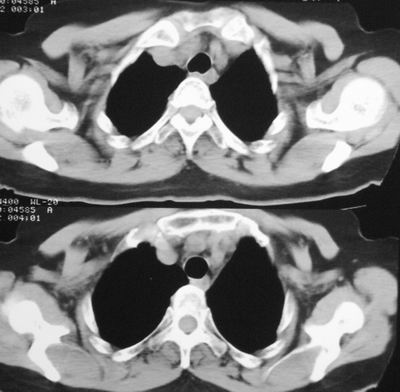

患者,女,64岁,4年前左腮腺"多形性"腺瘤手术治疗史.现复查胸部ct见左下肺块状影,该影与原左腮腺手术是否有联系?

术前(4年前)ct报告书

表现:左腮腺增大,于颞下见一约2.6x1.6x2.0cm混杂密度块影,边界较模糊,增强前后ct值约5-32hu、7-67hu,邻近骨质及软组织未见明确破坏征象,咽旁间隙尚存,周围未见肿大淋巴结。

诊断:左侧腮腺增大,抗炎治疗后复查,请结合临床分析。

本次复查胸部ct

左下肺癌伴左肺门淋巴结转移

支持考虑左下肺原发性肺癌,并左肺门淋巴结肿大

左下周围型肺癌伴左肺门淋巴结及右肺转移可能性大.